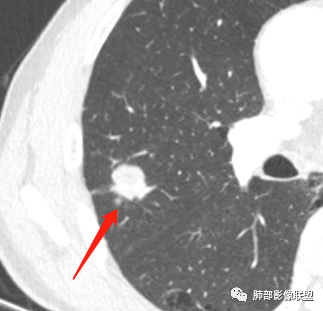

影像学改变:

1.右肺上叶后段类圆形结节影,密度不均,有坏死空洞,坏死比较彻底,内外壁都较清楚。

2.病灶有浅切迹,没有深分叶,毛刺大多细长且柔软。

3.可见棘状突起及胸膜牵拉,但未见胸膜凹陷。

什么意思?结节影有牵拉的动作,但似乎“出工不出力”,收缩力羸弱!

4.病灶轻到中度强化。病灶内血管走行较完好,病灶旁血管局部显示粗大。

5.支气管关系不确定。

6.灶周见小结节影(卫星灶),边界不甚清晰。